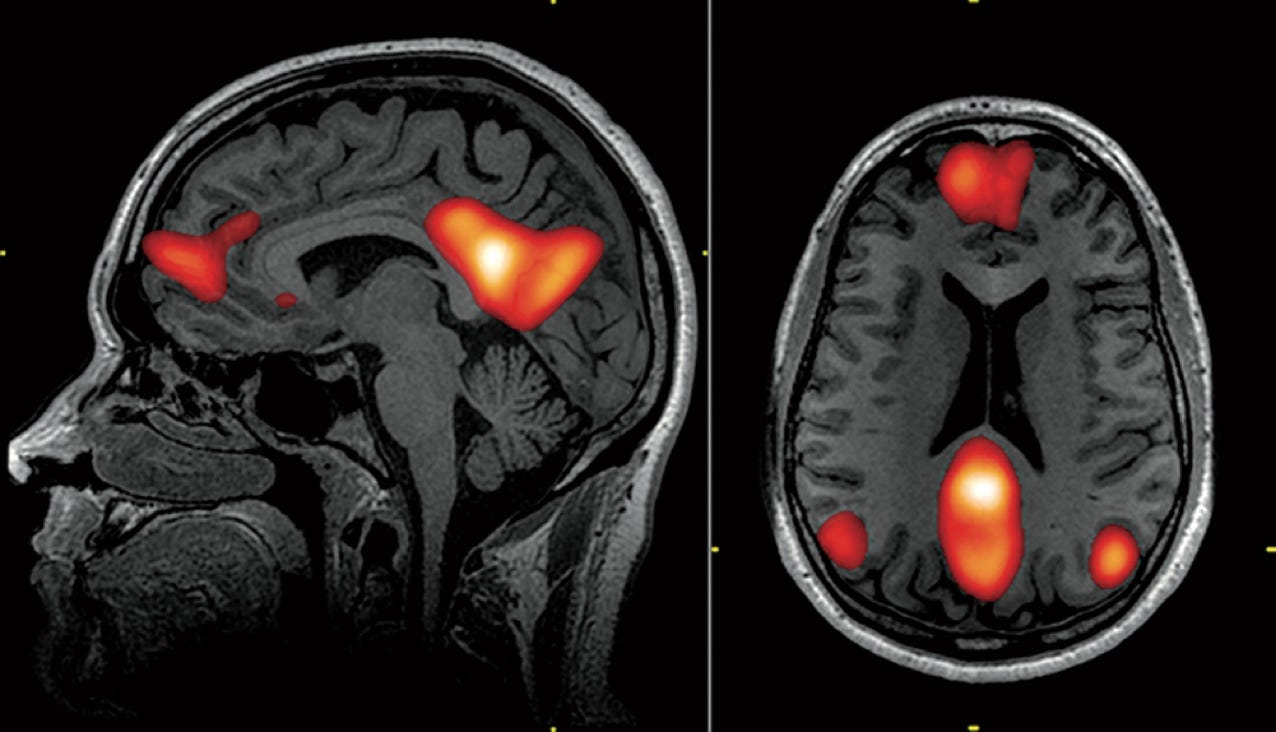

Magnetresonanztomografie von Hirnarealen im Default-Mode- Netzwerk (Abb.: John Graner, Neuroimaging Department, National Intrepid Center of Excellence, Walter Reed National Military Medical Center, USA).